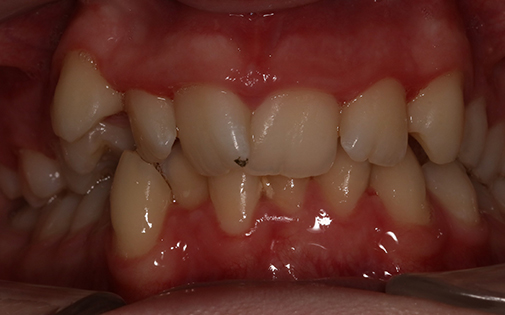

This teenage patient had a very crowded top left canine tooth as well as an underbite. He was successfully treated with Invisalign clear aligners in 22 months.